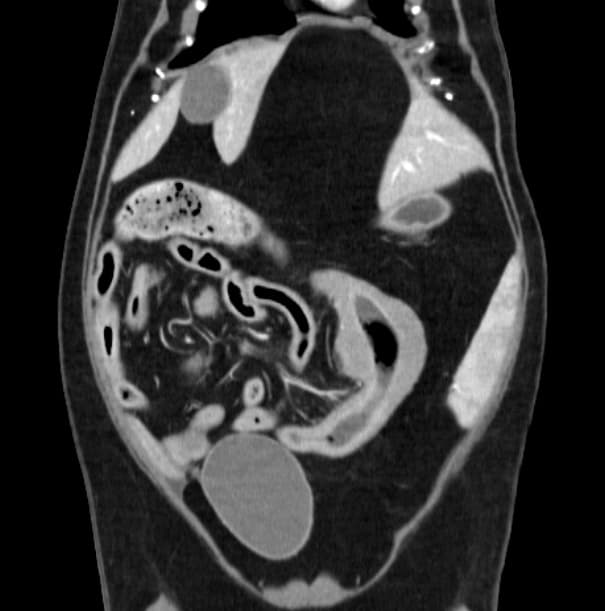

동탄 1 신도시 최초 Aquilion CX/128 slice CT를 동물병원에 도입하였습니다. 최고 사양 CT 모델 Aquilion CX/128 slice를 활용하여 0.5 mm의 얇은 128개의 단면 영상을 신속히 획득 할 수 있어 마취 시간을 단축시킬 수 있습니다. 또한, 128 슬라이스의 고화질의 CT 영상을 통해 영상 왜곡을 최소화하고 X-ray에서는 확인하기 힘든 5 mm 이하의 미세 병변도 확인이 가능하여 정확한 진단을 할 수 있습니다. 심화 진단이 필요한 경우, 조영제 인젝터를 통한 동맥기 촬영으로 종양 유래 확인, 간 질환 진단, 심혈관계 진단이 용이합니다. 저희 동탄시티동물의료센터에서는 본원 환자뿐 아니라 1차 동물 병원과의 CT 촬영 의뢰 시스템을 통해서 원활한 협진이 가능하도록 최선을 다하고 있습니다.

0164 채널 CT 촬영을 통해서 신속하게 고화질 영상을 얻어, 종양 유래 확인 및 전이 평가, 간문맥단락증(PSS), 선천적 뼈 기형과 같은 심화된 진단을 할 수 있습니다.

64채널 검출기 시스템 128

슬라이스 이미징 능력

고속 스캔 및 높은 해상도 제공

저선량 기술 적용으로 환자 방사선 노출 감소

흉복부, 골격계 전반의 선명하고 우수한 영상을 저선량으로 촬영이 가능